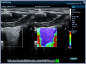

Neben einem ausführlichen Gespräch, der Anamnese, Zeit und Zuwendung gehören auch die Anwendung von wissenschaftlich evaulierten diagnostischen Verfahren zu einer guten Eingangsuntersuchung. Ich freue mich Ihnen in meiner Praxis deshalb nun auch die Ultraschalluntersuchung mit modernster Technik, einem mindray Consona N6 anbieten zu können.

- Darstellung der Schilddrüse - Darstellung der hirnversorgenden Gefäße mit Messung der Intimadicke (IMD) - Ultraschall des Herzens z. B. Stenose / Dichtigkeit der Herzklappen, Wandbewegungsstörungen,... - Ultraschall des Bauchraumes wie Leber, Gallenblase, Nieren, Blase, Milz. - Gefäßdarstellung

Video Farbdoppler der Halsarterie zur Darstellung der Durchblutung Video Farbdoppler der Niere zur Darstellung der Durchblutung Video Herzultraschall eines gesundes Herzens mit guter Pumpfunktion Video Herzultraschall mit eingeschränkter Pumpfunktion und vergrößerten Vorhöfen Video Herzultraschall bei Herzinsuffizienz und undichter Herzklappe